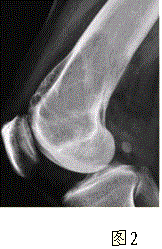

问题 患者女,35岁,左膝关节隐痛1年余,近1周加重,活动后明显疼痛。查体:左股骨下端外侧肿胀,压痛。行左膝关节正侧位CR,并行左膝关节CT扫描,见下图。 根据膝关节CR和CT影像,你认为此病例的影像学表现有

选项 A.左股骨外髁溶骨性骨质破坏 B.病灶呈明显膨胀 C.病变边缘清晰,有明显硬化缘 D.CT示左股骨外髁骨皮质不完整 E.病灶边缘可见骨膜反应,Codman三角形成 F.病灶周围软组织肿胀

答案 ABDF